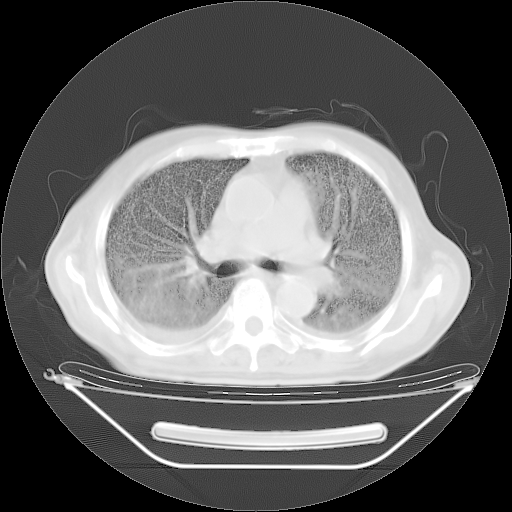

今天复查肺部CT,发现双肺广泛磨玻璃样改变。所以我把3月19日和5月9日相隔50天的肺部CT上传。请大家会诊。

2009年3月19日肺部CT片。

2009年3月19日肺部CT

大致读了系列胸部CT:纵隔窗无明显异常,肺窗:从4、27至今:主要是双肺中下野外带可见毛玻璃样改变,目前处于急性肺泡炎阶段,至于原因考虑1、结替组织或胶原血管性疾病所致?2、恶性疾病如恶组在肺部所致的表现或细支气管肺泡癌?3、药物或其它原因如肺蛋白沉着症所致肺泡炎目前不太可能?总之,明天就去请我院的呼吸科、感染科、血液科和临免专家会诊哈。